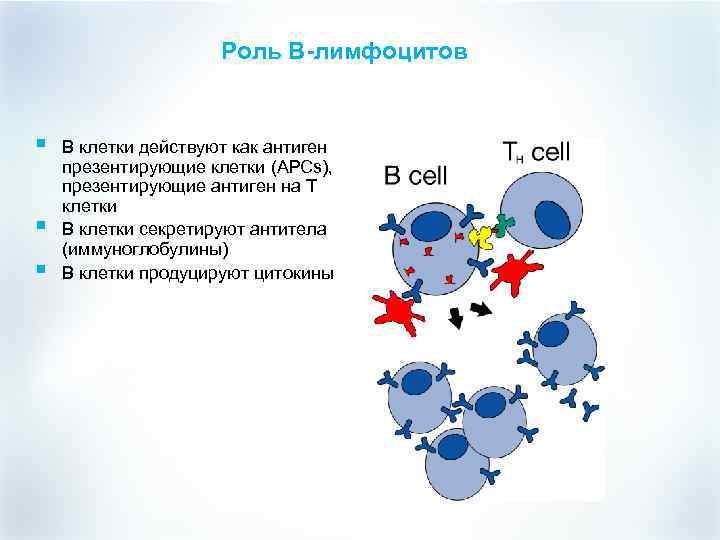

Роль В-лимфоцитов § § § B клетки действуют как антиген презентирующие клетки (APCs), презентирующие антиген на Т клетки B клетки секретируют антитела (иммуноглобулины) В клетки продуцируют цитокины

Роль В-лимфоцитов § § § B клетки действуют как антиген презентирующие клетки (APCs), презентирующие антиген на Т клетки B клетки секретируют антитела (иммуноглобулины) В клетки продуцируют цитокины